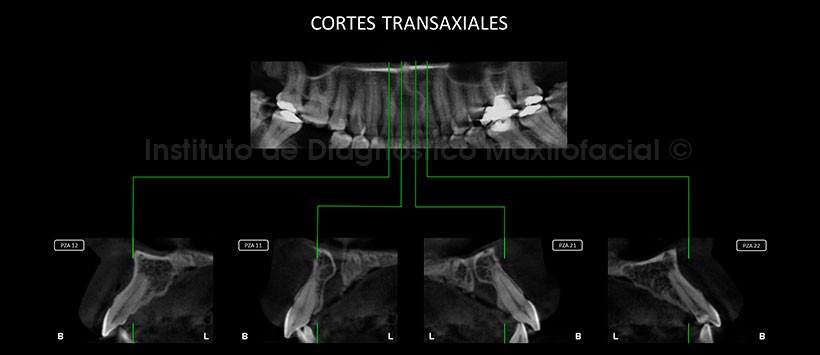

A la evaluación tomográfica se pudo determinar el aumento de tamaño y volumen del conducto nasopalatino, con una medida volumétrica aproximada de 0.2 cm(Figura 2).  Así mismo en los cortes transaxiales se observa que este aumento de tamaño todavía no afecta a las piezas dentarias adyacentes sin embargo existe un  desplsamaiento predominante de la tabla ósea vestibular del conducto nasopalatino (Figura 3). En los cortes tangenciales se aprecia que la extensión en un sentido mesiodistal, la cual se extiende hasta los segmentos radiculares de las piezas 12 y 22, así mismo se puede apreciar una variación anatómica en el trayecto del conducto, existiendo dos conductos laterales que convergen en un mismo conducto (Figura 4).